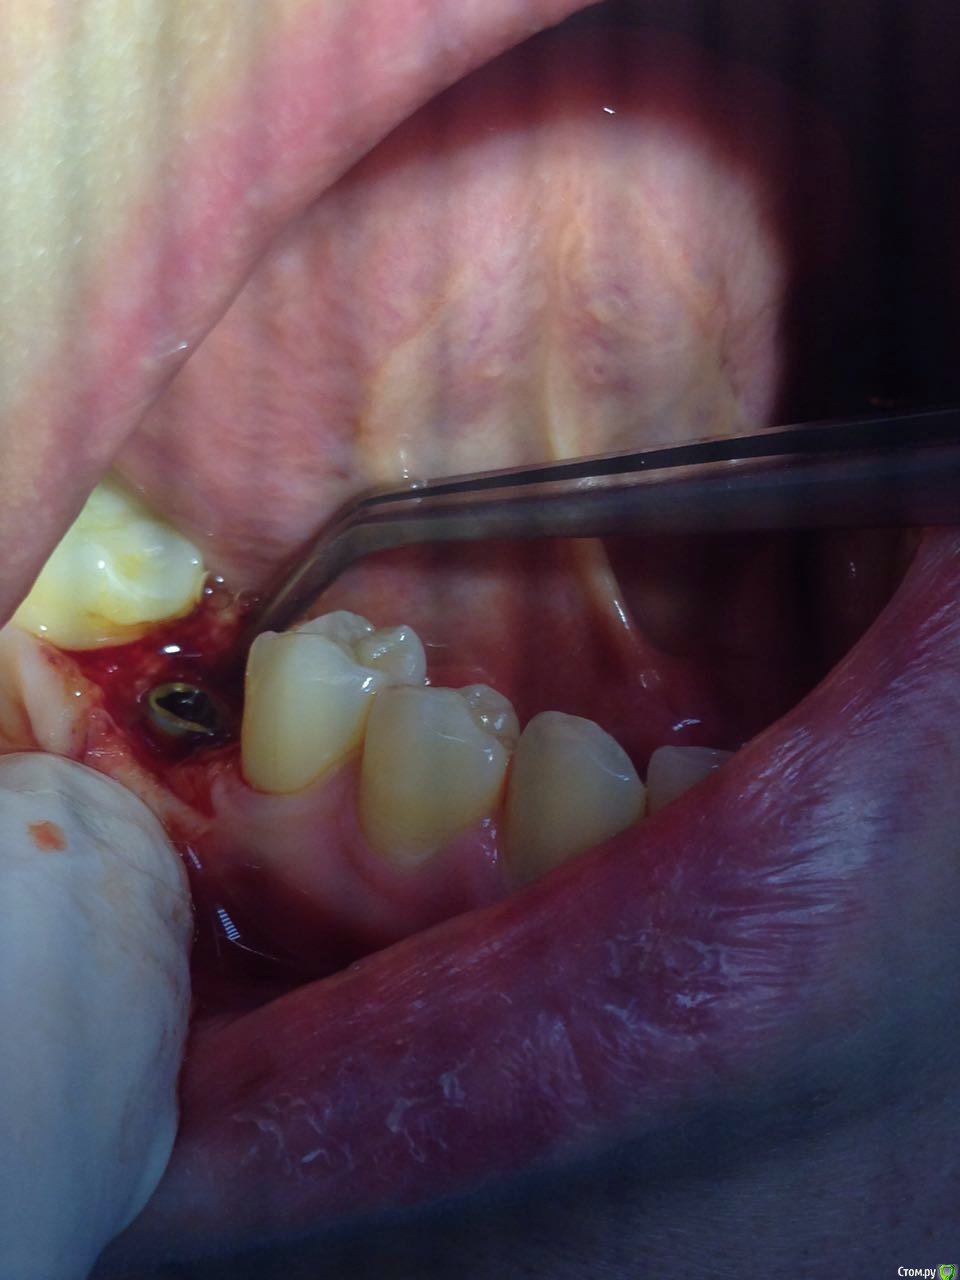

Madira Опубликовано 16 марта, 2016 Автор Поделиться Опубликовано 16 марта, 2016 Врач сегодня сфотографировала 2 нижних импланта. Что-то по этим фотографиям можно сказать? Насколько криичная ситуация? Ссылка на комментарий

diesel87 Опубликовано 16 марта, 2016 Поделиться Опубликовано 16 марта, 2016 То же что и по снимку, резорбция кости по шейке имплантатов. И так же, судя по нему, скорее всего нижние 2 импланта не были установлены вровень с костью, скорее всего на 0,5-1,0 мм над уровнем кости. С установкой фдм возможно картина станет лучше, отдохните пока, погуляйте 3-4 недели с ними, мягкие ткани должны успокоиться. Ссылка на комментарий

Madira Опубликовано 16 марта, 2016 Автор Поделиться Опубликовано 16 марта, 2016 (изменено) Спасибо. Врач сказала, что резорбция произошла не со всех сторон импланта. Это на последних фото как-то видно? Или видно четко, что он именно не докручен со всех сторон одинаково? 3 недели с удовольствием отдохну)))Мне моя врач тоже самое и посоветовала)) Но что дальше? Жить с ними не надеясь на их долговечность? Изменено 16 марта, 2016 пользователем Madira Ссылка на комментарий